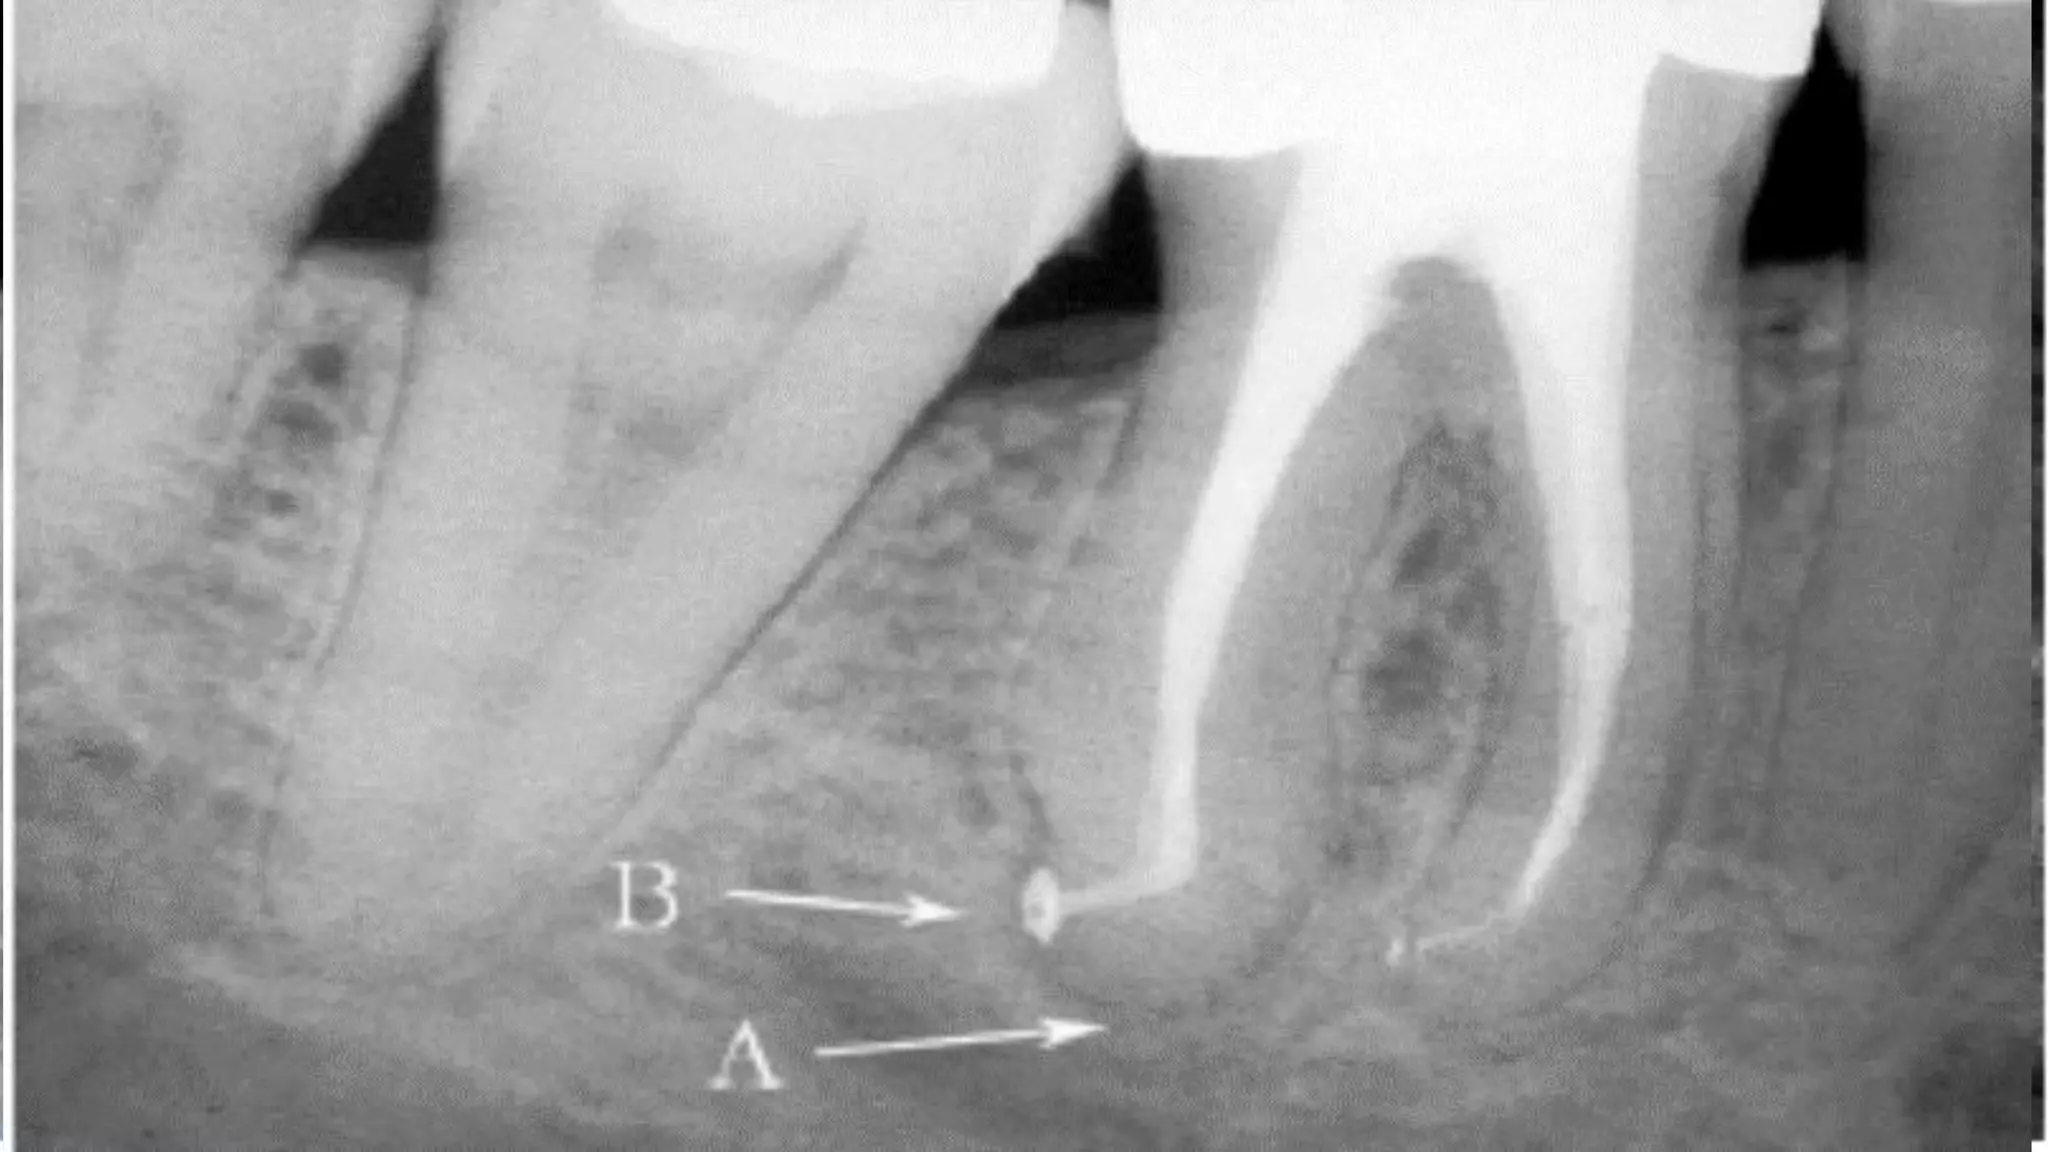

A.Anatomic apex

B.Apical constriction (minor diameter)

F. Apical foramen

The mean distance between the major and minor diameters

0.5 mm in a young person and 0.67 mm in an older individual.

The increased length in older individuals is due to the increased

buildup of cementum

According to Kuttler, the narrowest diameter of

the canal is definitely not at the site of exiting of the

canal from the tooth but usually occurs within the dentin,

just prior to the initial layers of cementum.

He referred to this position as the minor diameter

of the canal, although others call it the apical constriction.

The diameter of the canal at the site of exiting from the

tooth (major diameter) was found to be approximately

twice as wide as minor diameter. This means that the

longitudinal view of the canal as a tapering funnel to the

tip of the root is incorrect.